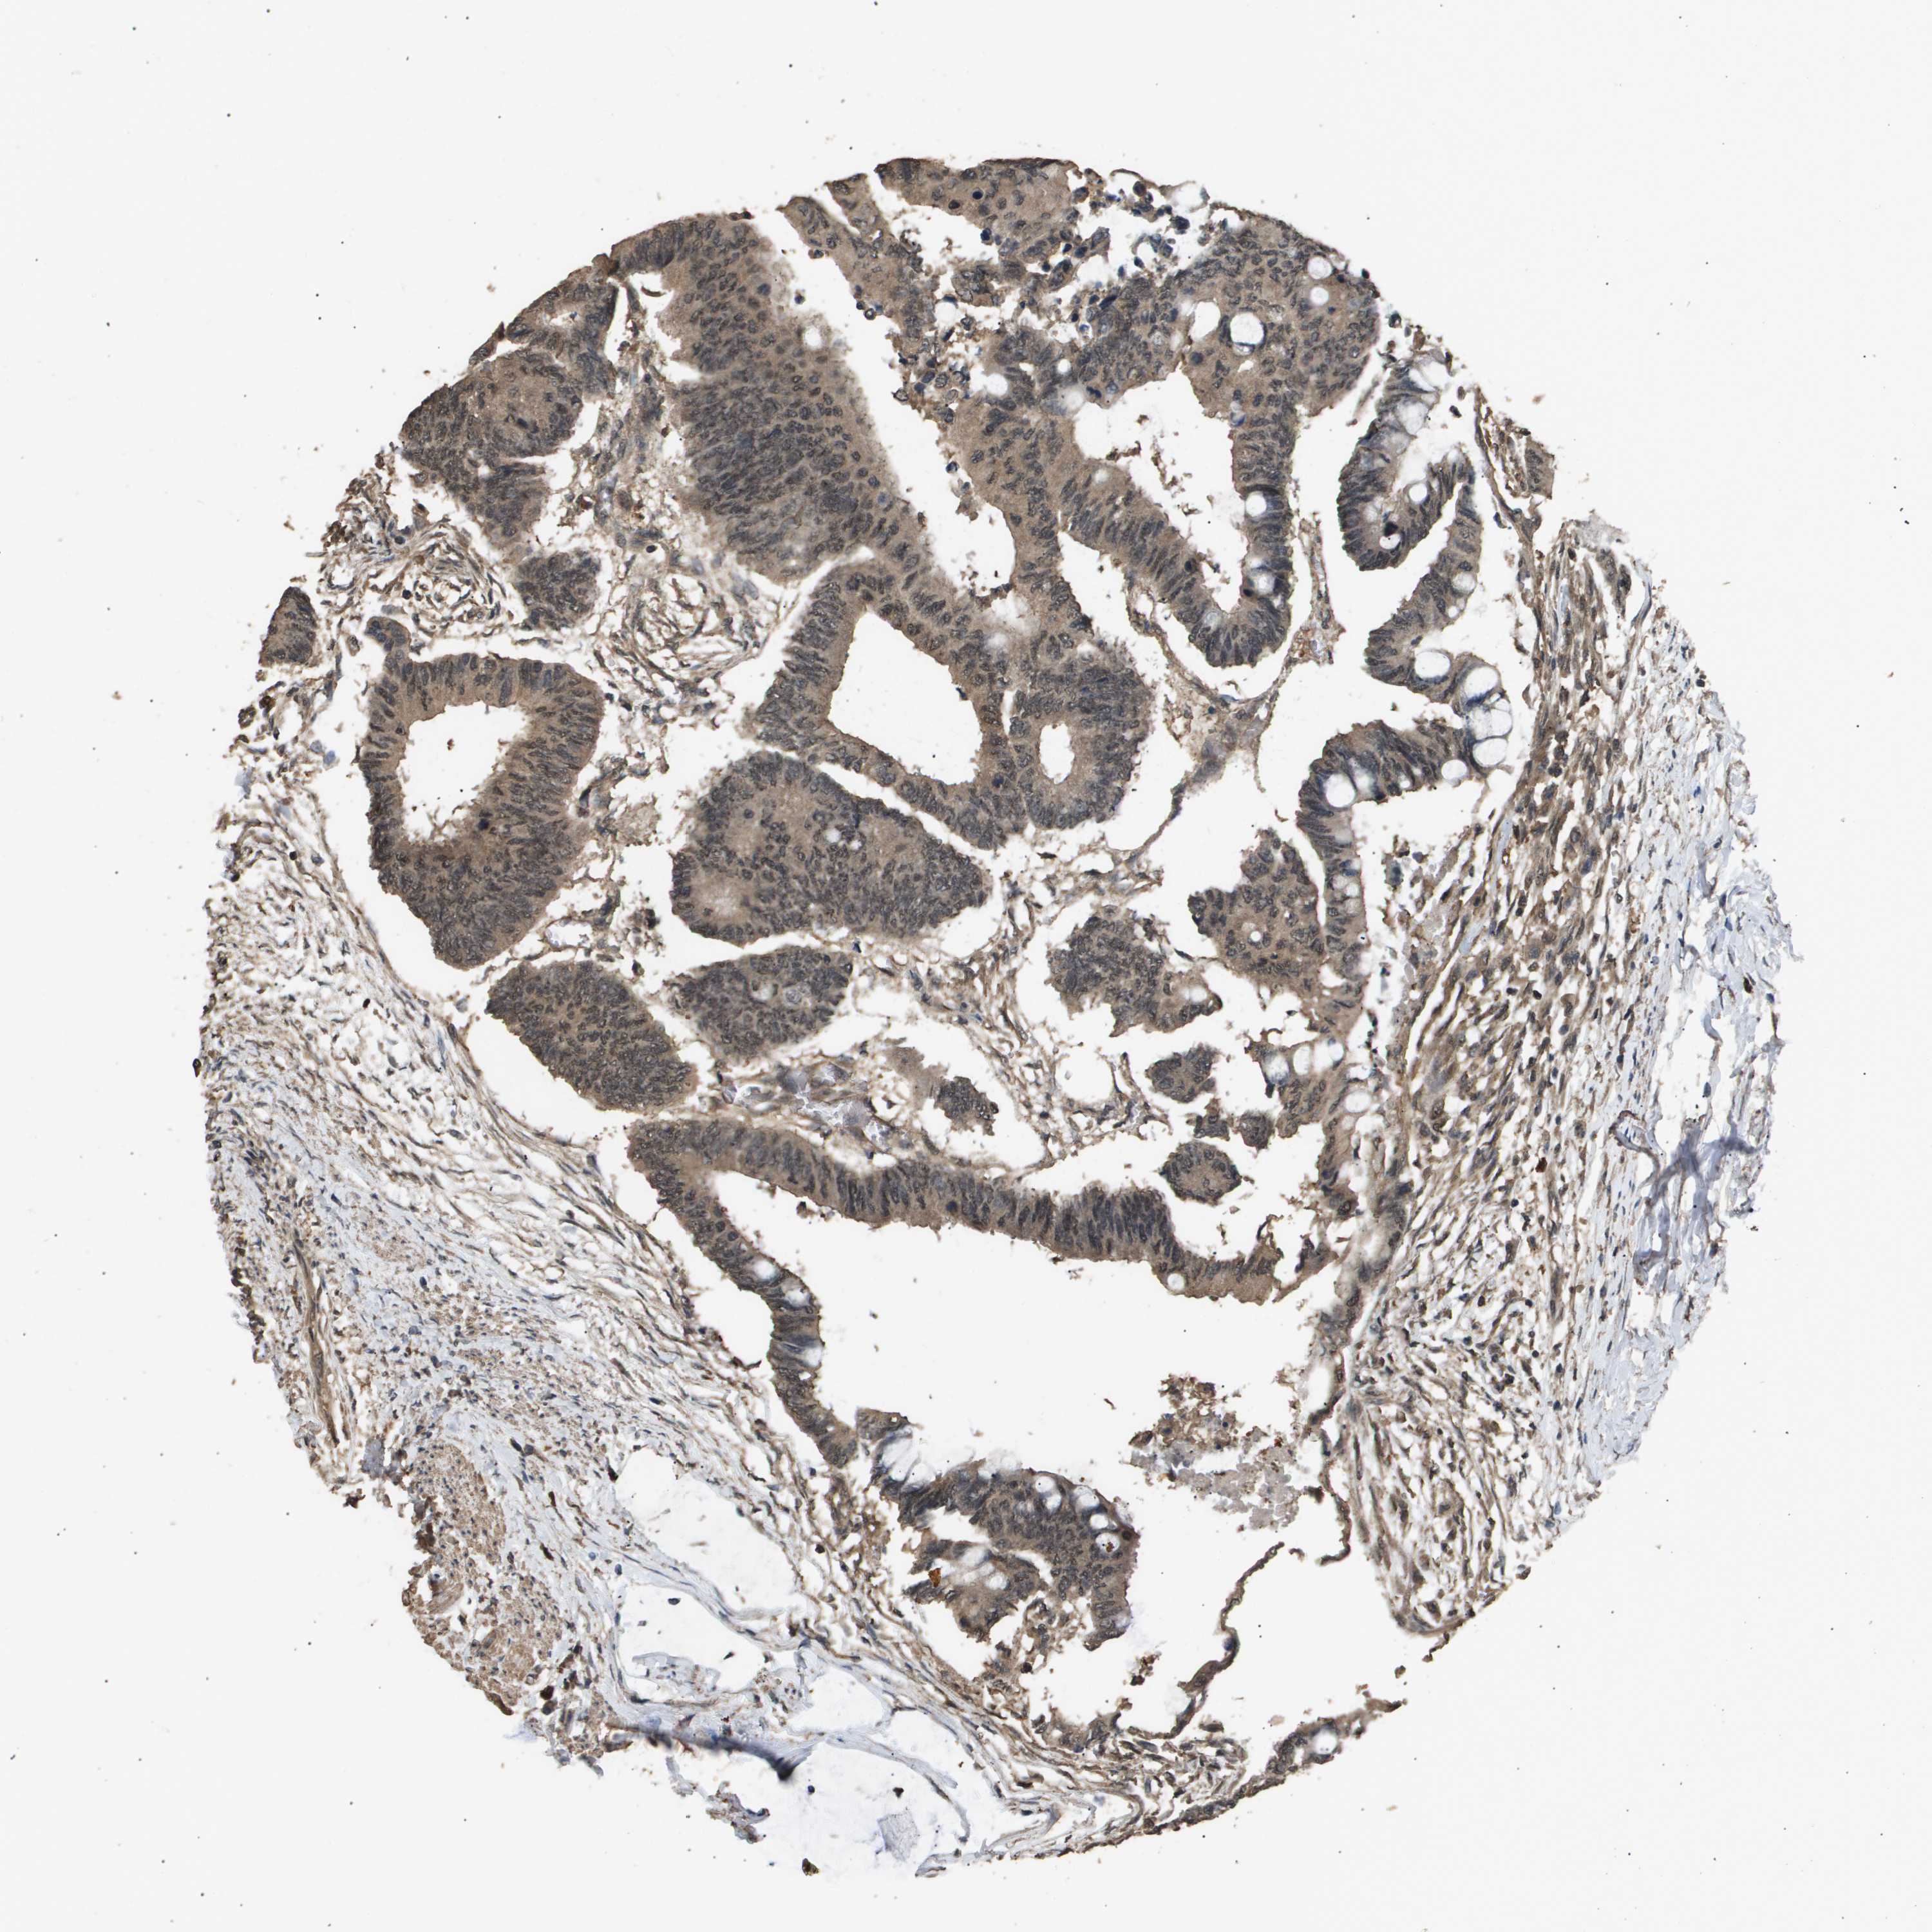

CANCER COLORECTAL CANCER Show tissue menu

Colorectal cancer

Human cancer

Colon adenocarcinoma